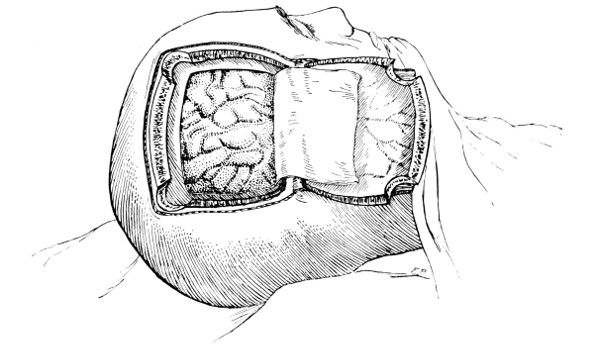

Fig. 17. First Stage in the Formation of an Osteoplastic Flap. Gigli’s saw, protected from the dura mater by the special director, passing between the two trephine-holes. For further description, see text.

[27]

Fig. 18. Second Stage in the Formation of an Osteoplastic Flap. The bone-flap turned down and the dura mater exposed.

Fig. 19. Third Stage in the Formation of an Osteoplastic Flap. The dural flap turned down and the brain exposed. Note the relation of the scalp, bone, and dural incisions to one another.